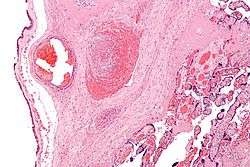

| Intermediate magnification micrograph of the placental disc showing a thrombosed fetal vein, as may be seen in fetal thrombotic vasculopathy. H&E stain. | |

High mag.